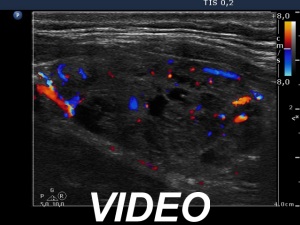

100 consecutive patients with thyroid nodule - Case 1. |

Clinical presentation: a 56-year-old man was referred for follow-up examination of a thyroid nodule. The patient was known harboring a nodule for 4 years. Previous cytology from the "dominant nodule in the left thyroid" resulted in benign lesion in another institute. The patient had no complaints.

Palpation: a firm nodule in the right lobe and a nodular part in the left thyroid.

Functional state: euthyroidism (TSH 1.33 mIU/L).

Ultrasonography. The thyroid was echonormal. There were two moderately hypoechogenic nodules in the ventromedial part of the right lobe. One of them presented irregular borders, hyperechogenic granules and cystic degeneration. The left thyroid contained several nodules with different echo structures.

Cytology was performed from the nodule in the right lobe and resulted in benign, follicular proliferation..